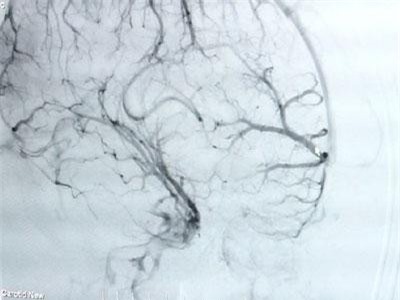

Nam bệnh nhân 28 tuổi nhập viện trong tình trạng đau đầu, nôn ói được bác sĩ chẩn đoán xuất huyết não. Khai thác bệnh sử ghi nhận, trước khi nhập viện, người bệnh đã phải đối mặt với nhiều căng thẳng, áp lực trong công việc.